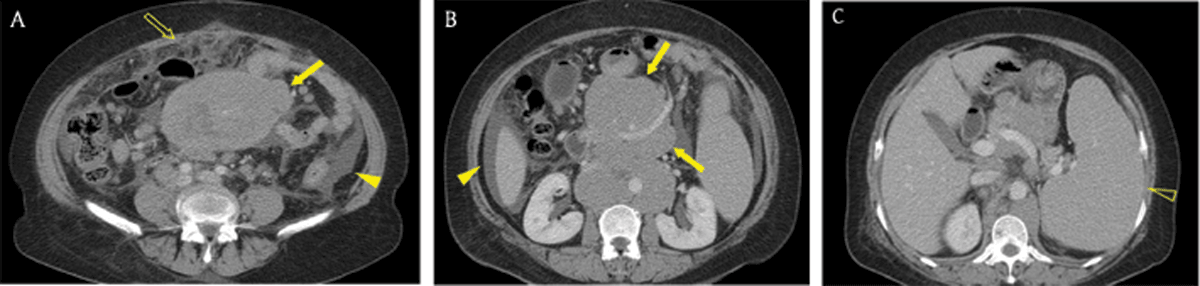

Figure 1

A 40-year-old man with advanced gastric cancer and peritoneal carcinomatosis. Axial portal venous phase CT images revealed multifocal discrete nodules (arrowheads) in the peritoneal cavity, peritoneal enhancement and thickening (arrow), ascites, and omental haziness (open arrow). Note the metastatic lymphadenopathy around the stomach (open arrowheads).